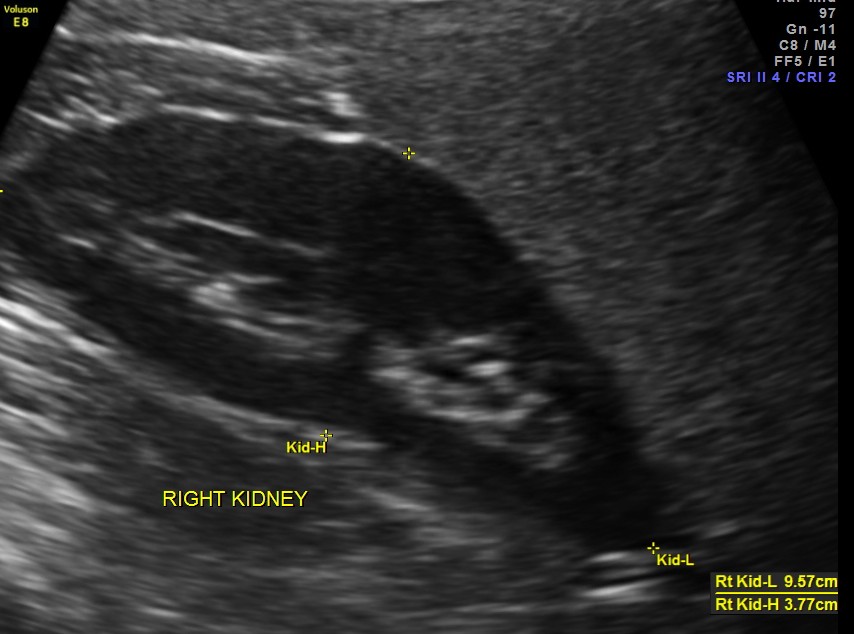

Ultrasound revealed normal liver, gall bladder, pancreas, spleen ,post menopausal shrunk uterus and normal right kidney.

The left kidney showed a calculus.